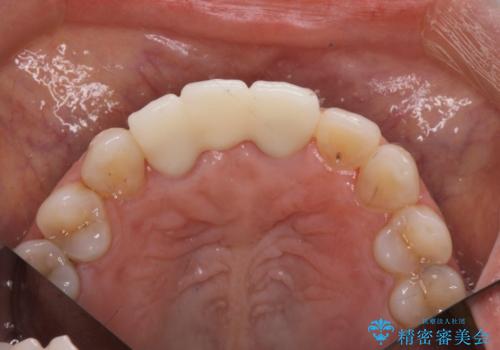

歯周外科をおこなったことで歯ぐきのラインを整え、脱離しないような前歯のブリッジを作製することができました。